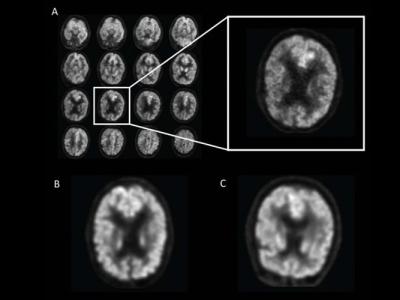

美国加州大学三藩市分校研AI检测脑图像

研究人员让AI学习深度运算法检测脑图像,及早发现早老性痴呆症...